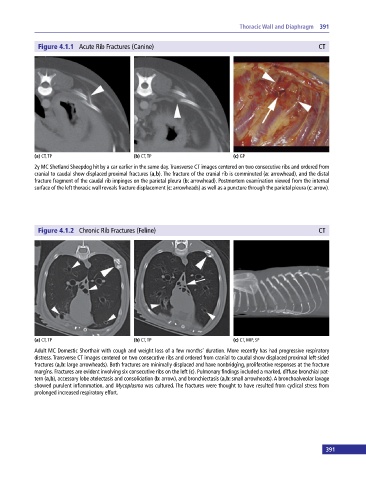

Figure 4.1.1 Acute Rib Fractures (Canine) CT

2y MC Shetland Sheepdog hit by a car earlier in the same day. Transverse CT images centered on two consecutive ribs and ordered from

cranial to caudal show displaced proximal fractures (a,b). The fracture of the cranial rib is comminuted (a: arrowhead), and the distal

fracture fragment of the caudal rib impinges on the parietal pleura (b: arrowhead). Postmortem examination viewed from the internal

surface of the left thoracic wall reveals fracture displacement (c: arrowheads) as well as a puncture through the parietal pleura (c: arrow).

Figure 4.1.2 Chronic Rib Fractures (Feline) CT

Adult MC Domestic Shorthair with cough and weight loss of a few months’ duration. More recently has had progressive respiratory

distress. Transverse CT images centered on two consecutive ribs and ordered from cranial to caudal show displaced proximal left‐sided

fractures (a,b: large arrowheads). Both fractures are minimally displaced and have nonbridging, proliferative responses at the fracture

margins. Fractures are evident involving six consecutive ribs on the left (c). Pulmonary findings included a marked, diffuse bronchial pat-

tern (a,b), accessory lobe atelectasis and consolidation (b: arrow), and bronchiectasis (a,b: small arrowheads). A bronchoalveolar lavage

showed purulent inflammation, and Mycoplasma was cultured. The fractures were thought to have resulted from cyclical stress from

prolonged increased respiratory effort.